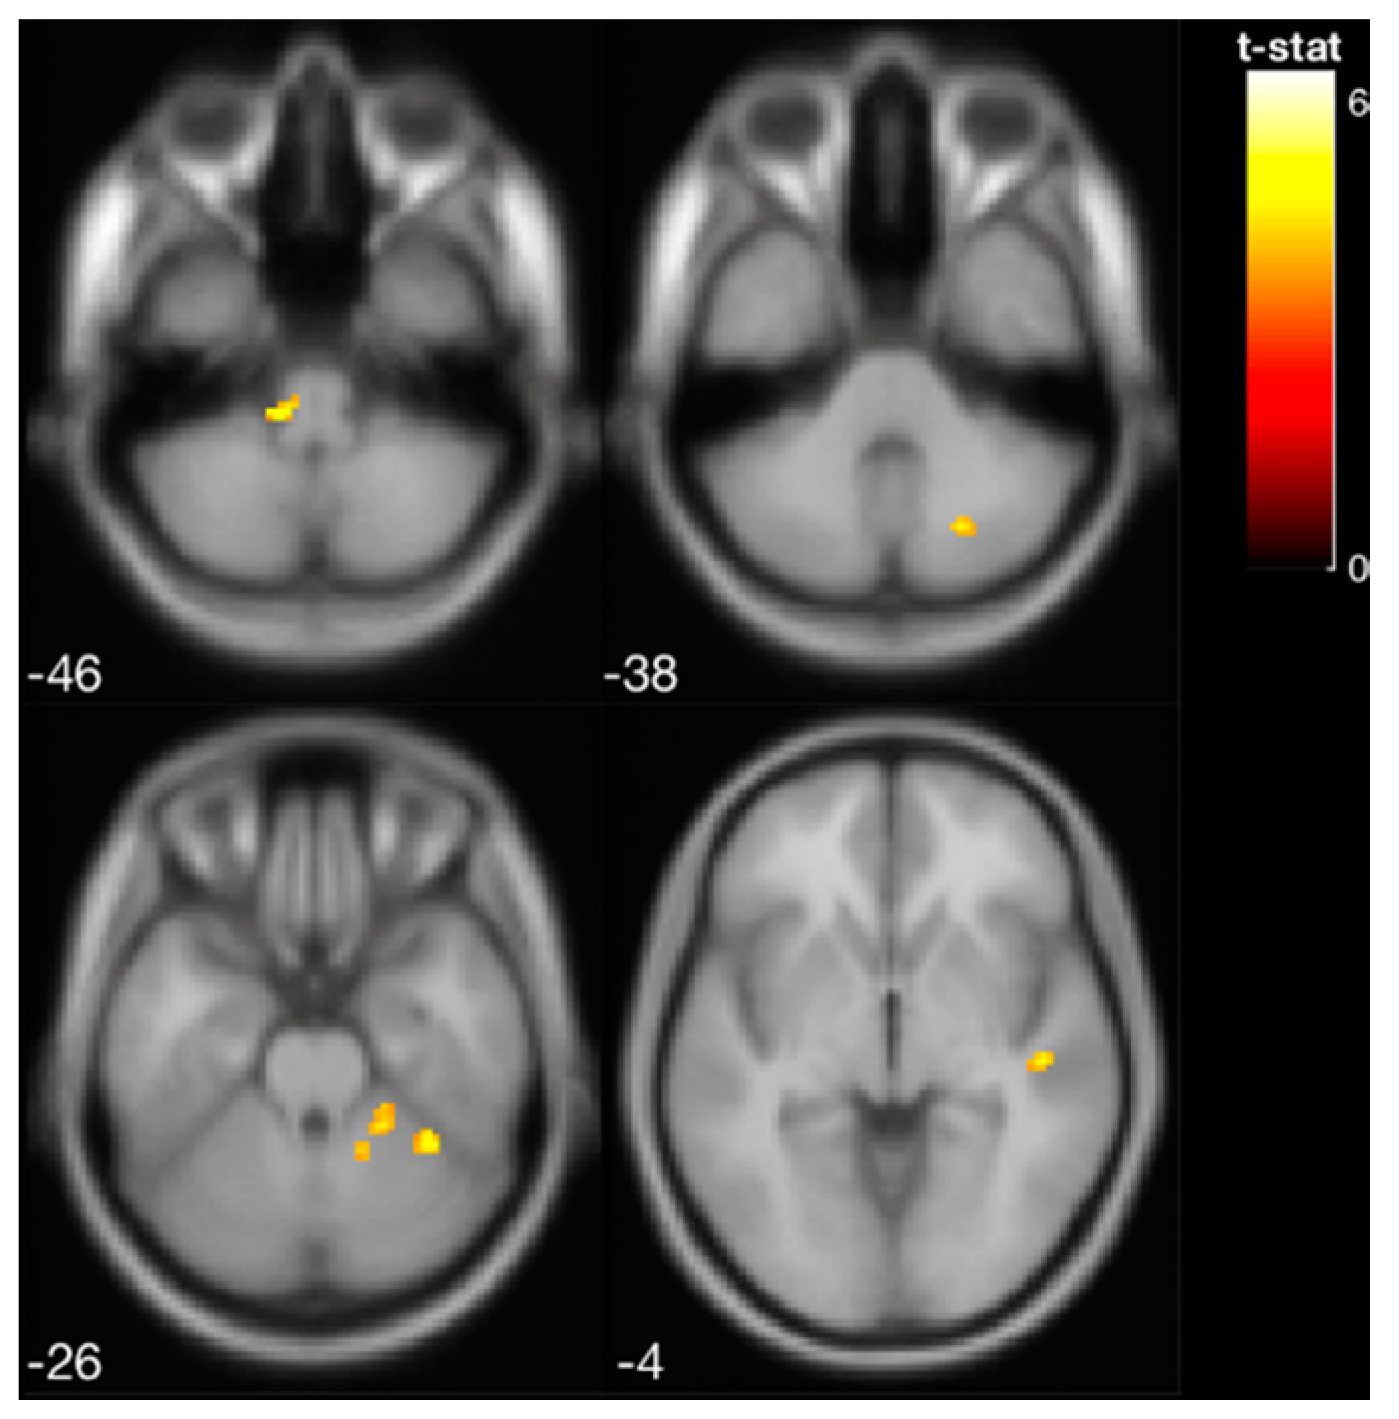

| Region Label | Extent | t-Value | MNI Coordinates | |||

|---|---|---|---|---|---|---|

| x | y | z | ||||

| Pre-training | Parietal Operculum Cortex | 72 | 9.983 | −46 | −36 | 22 |

| Post-training | Cerebellar lobules I–IV | 34 | 8.141 | 20 | −44 | −26 |

| Brainstem | 102 | 7.528 | 0 | −22 | −16 | |

| Middle Frontal Gyrus | 14 | 6.453 | 48 | 6 | 46 | |

| Middle Temporal Gyrus, temporooccipital part | 22 | 6.331 | −58 | −48 | −10 | |

| Middle Frontal Gyrus | 18 | 6.147 | −34 | 6 | 32 | |

| Inferior Frontal Gyrus, pars opercularis | 10 | 5.918 | −40 | 14 | 22 | |

| Post-training > Pre-training | Cerebellar lobules V–VI | 40 | 6.408 | 36 | −48 | −28 |

| Cerebellar lobules I–IV | 74 | 6.055 | 18 | −44 | −24 | |

| Vestibular Nucleus in Brainstem | 56 | 5.920 | −12 | −32 | −42 | |

| Superior Temporal Gyrus, posterior division | 30 | 4.761 | 48 | −22 | −4 | |

| Cerebellar lobule VIIB | 28 | 4.695 | 22 | −70 | −38 | |

| Cerebellar Crus I | 22 | 4.289 | −36 | −54 | −34 | |